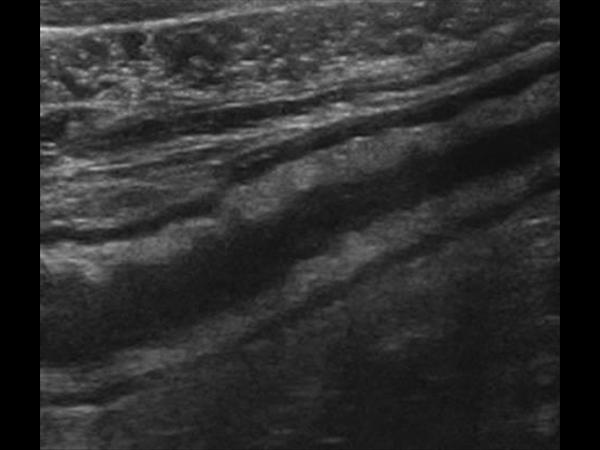

Viêm đại tràng

» Thông tin: Nam giới – 41 tuổi.

» Lâm sàng: Đau hạ vị.